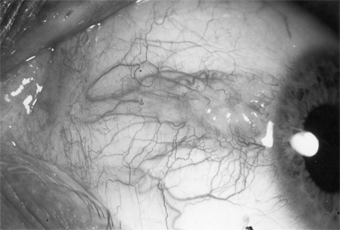

A pterygium is a fleshy, triangular encroachment of a pinguecula onto the cornea, usually on the nasal side bilaterally (Figure 5-22). It is thought to be an irritative phenomenon due to ultraviolet light, drying, and windy environments, since it is common in persons who spend much of their lives out of doors in sunny, dusty, or sandy, windblown surroundings. The pathologic findings in the conjunctiva are the same as those of pinguecula. In the cornea, there is replacement of Bowman's layer by hyaline and elastic tissue.

Figure 5-22

Figure 5-22: Pterygium encroaching on the cornea.